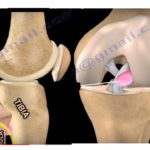

#Osteonecrosis Of The Knee

Courtesy: Prof Nabile Ebraheim, University of Toledo, Ohio, USA